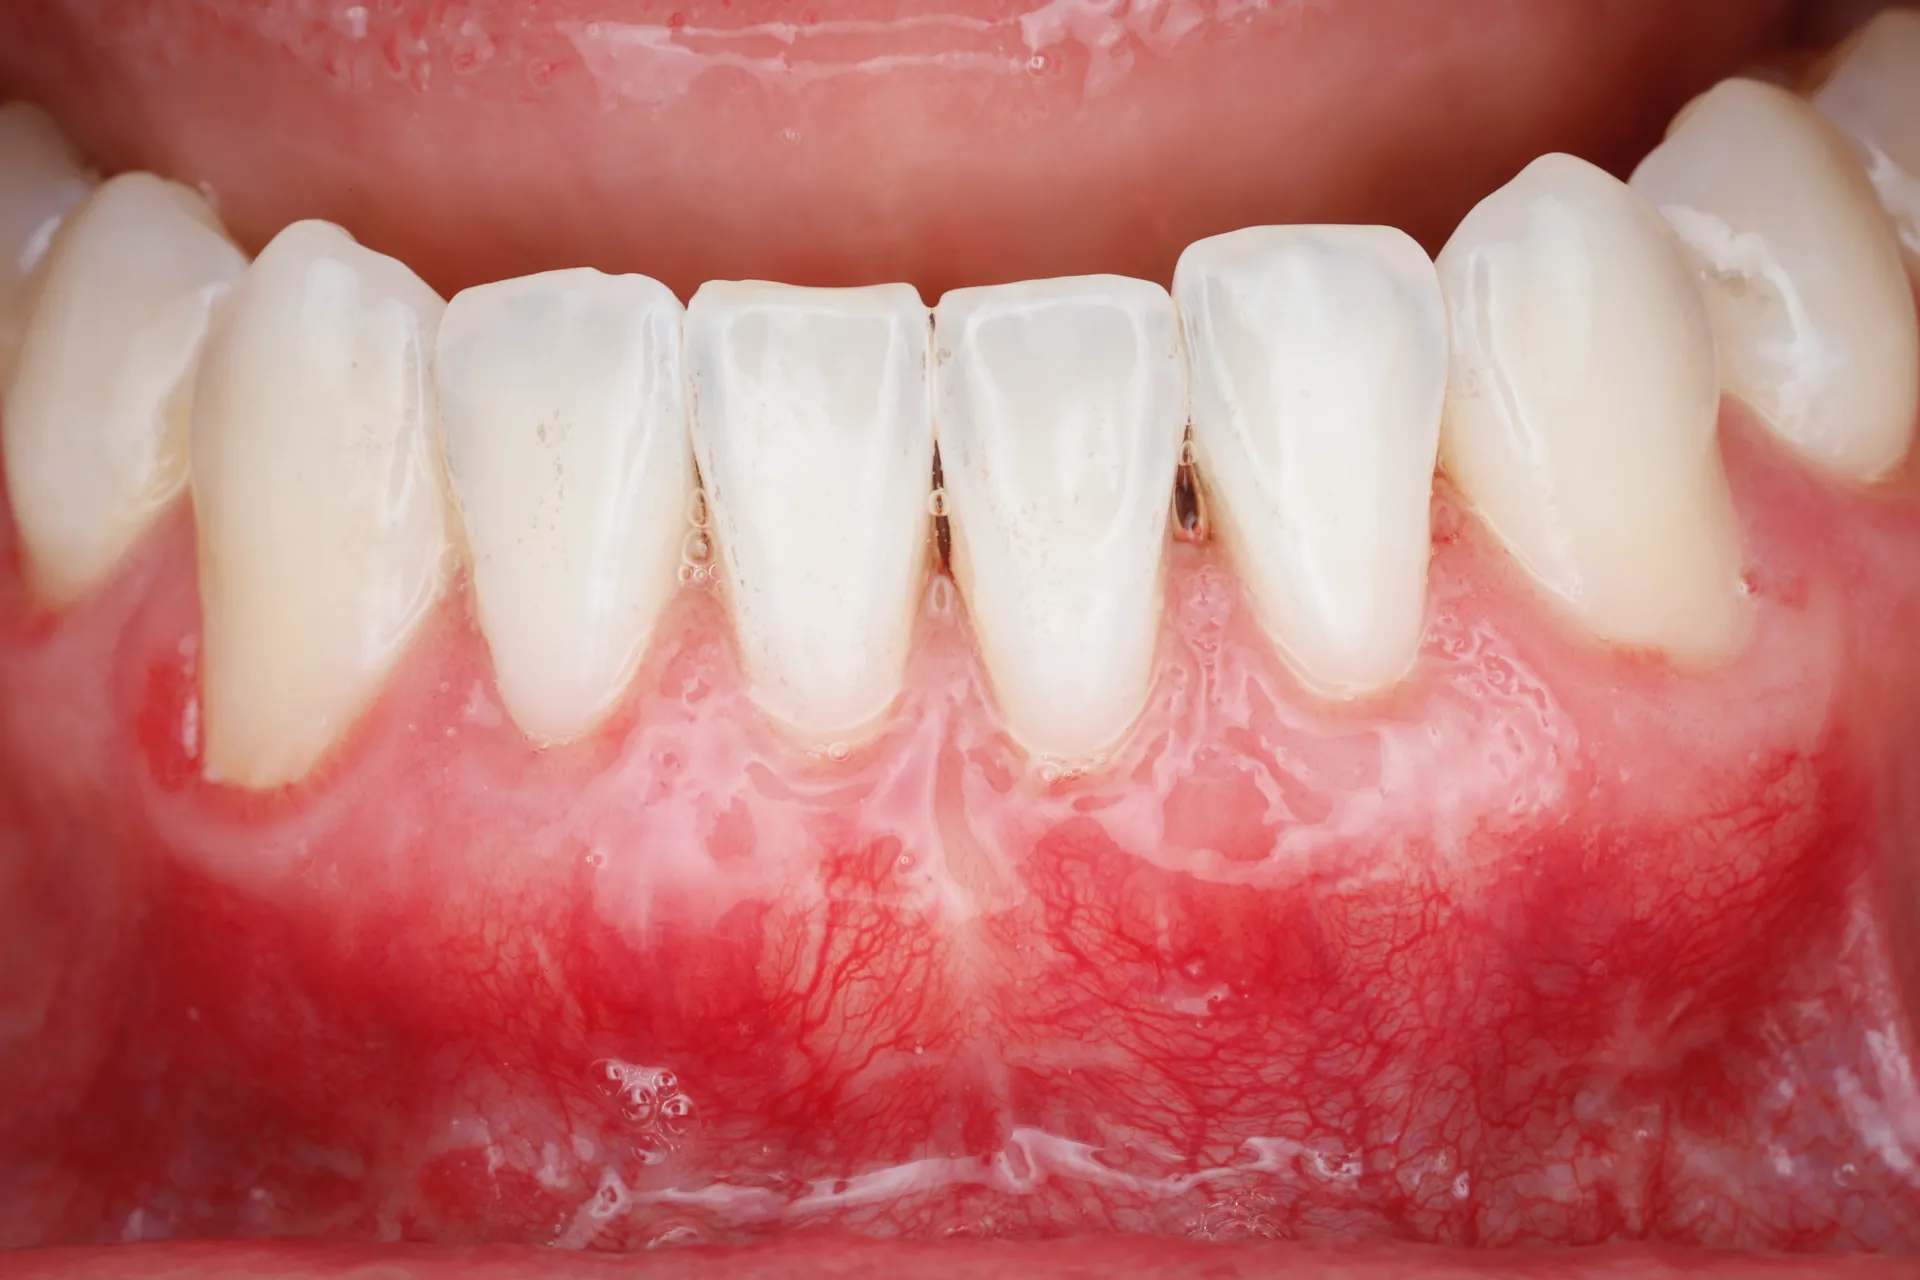

Gum Recession